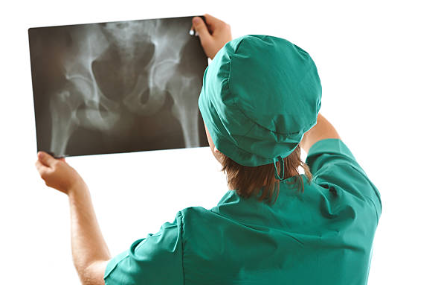

고관절 골절, 고관절 통증 증상과 치료 방법 알아보아요.

고관절 골절이란?

골다공증과 같은 뼈 약화 상태 또는 외상으로 인해 발생하는 대퇴골(허벅다리 뼈) 상단의 골절을 의미하는 것입니다. 일반적으로 낙상이나 직접적인 충격으로 인해 발생하며, 특히 고령자에서 흔히 일어날 수 있는 사고입니다. 고관절 골절치료는 주로 수술과 재활이 필요하며, 이는 환자의 이동과 삶의 질에 많은 영향을 미칠 수 있습니다.